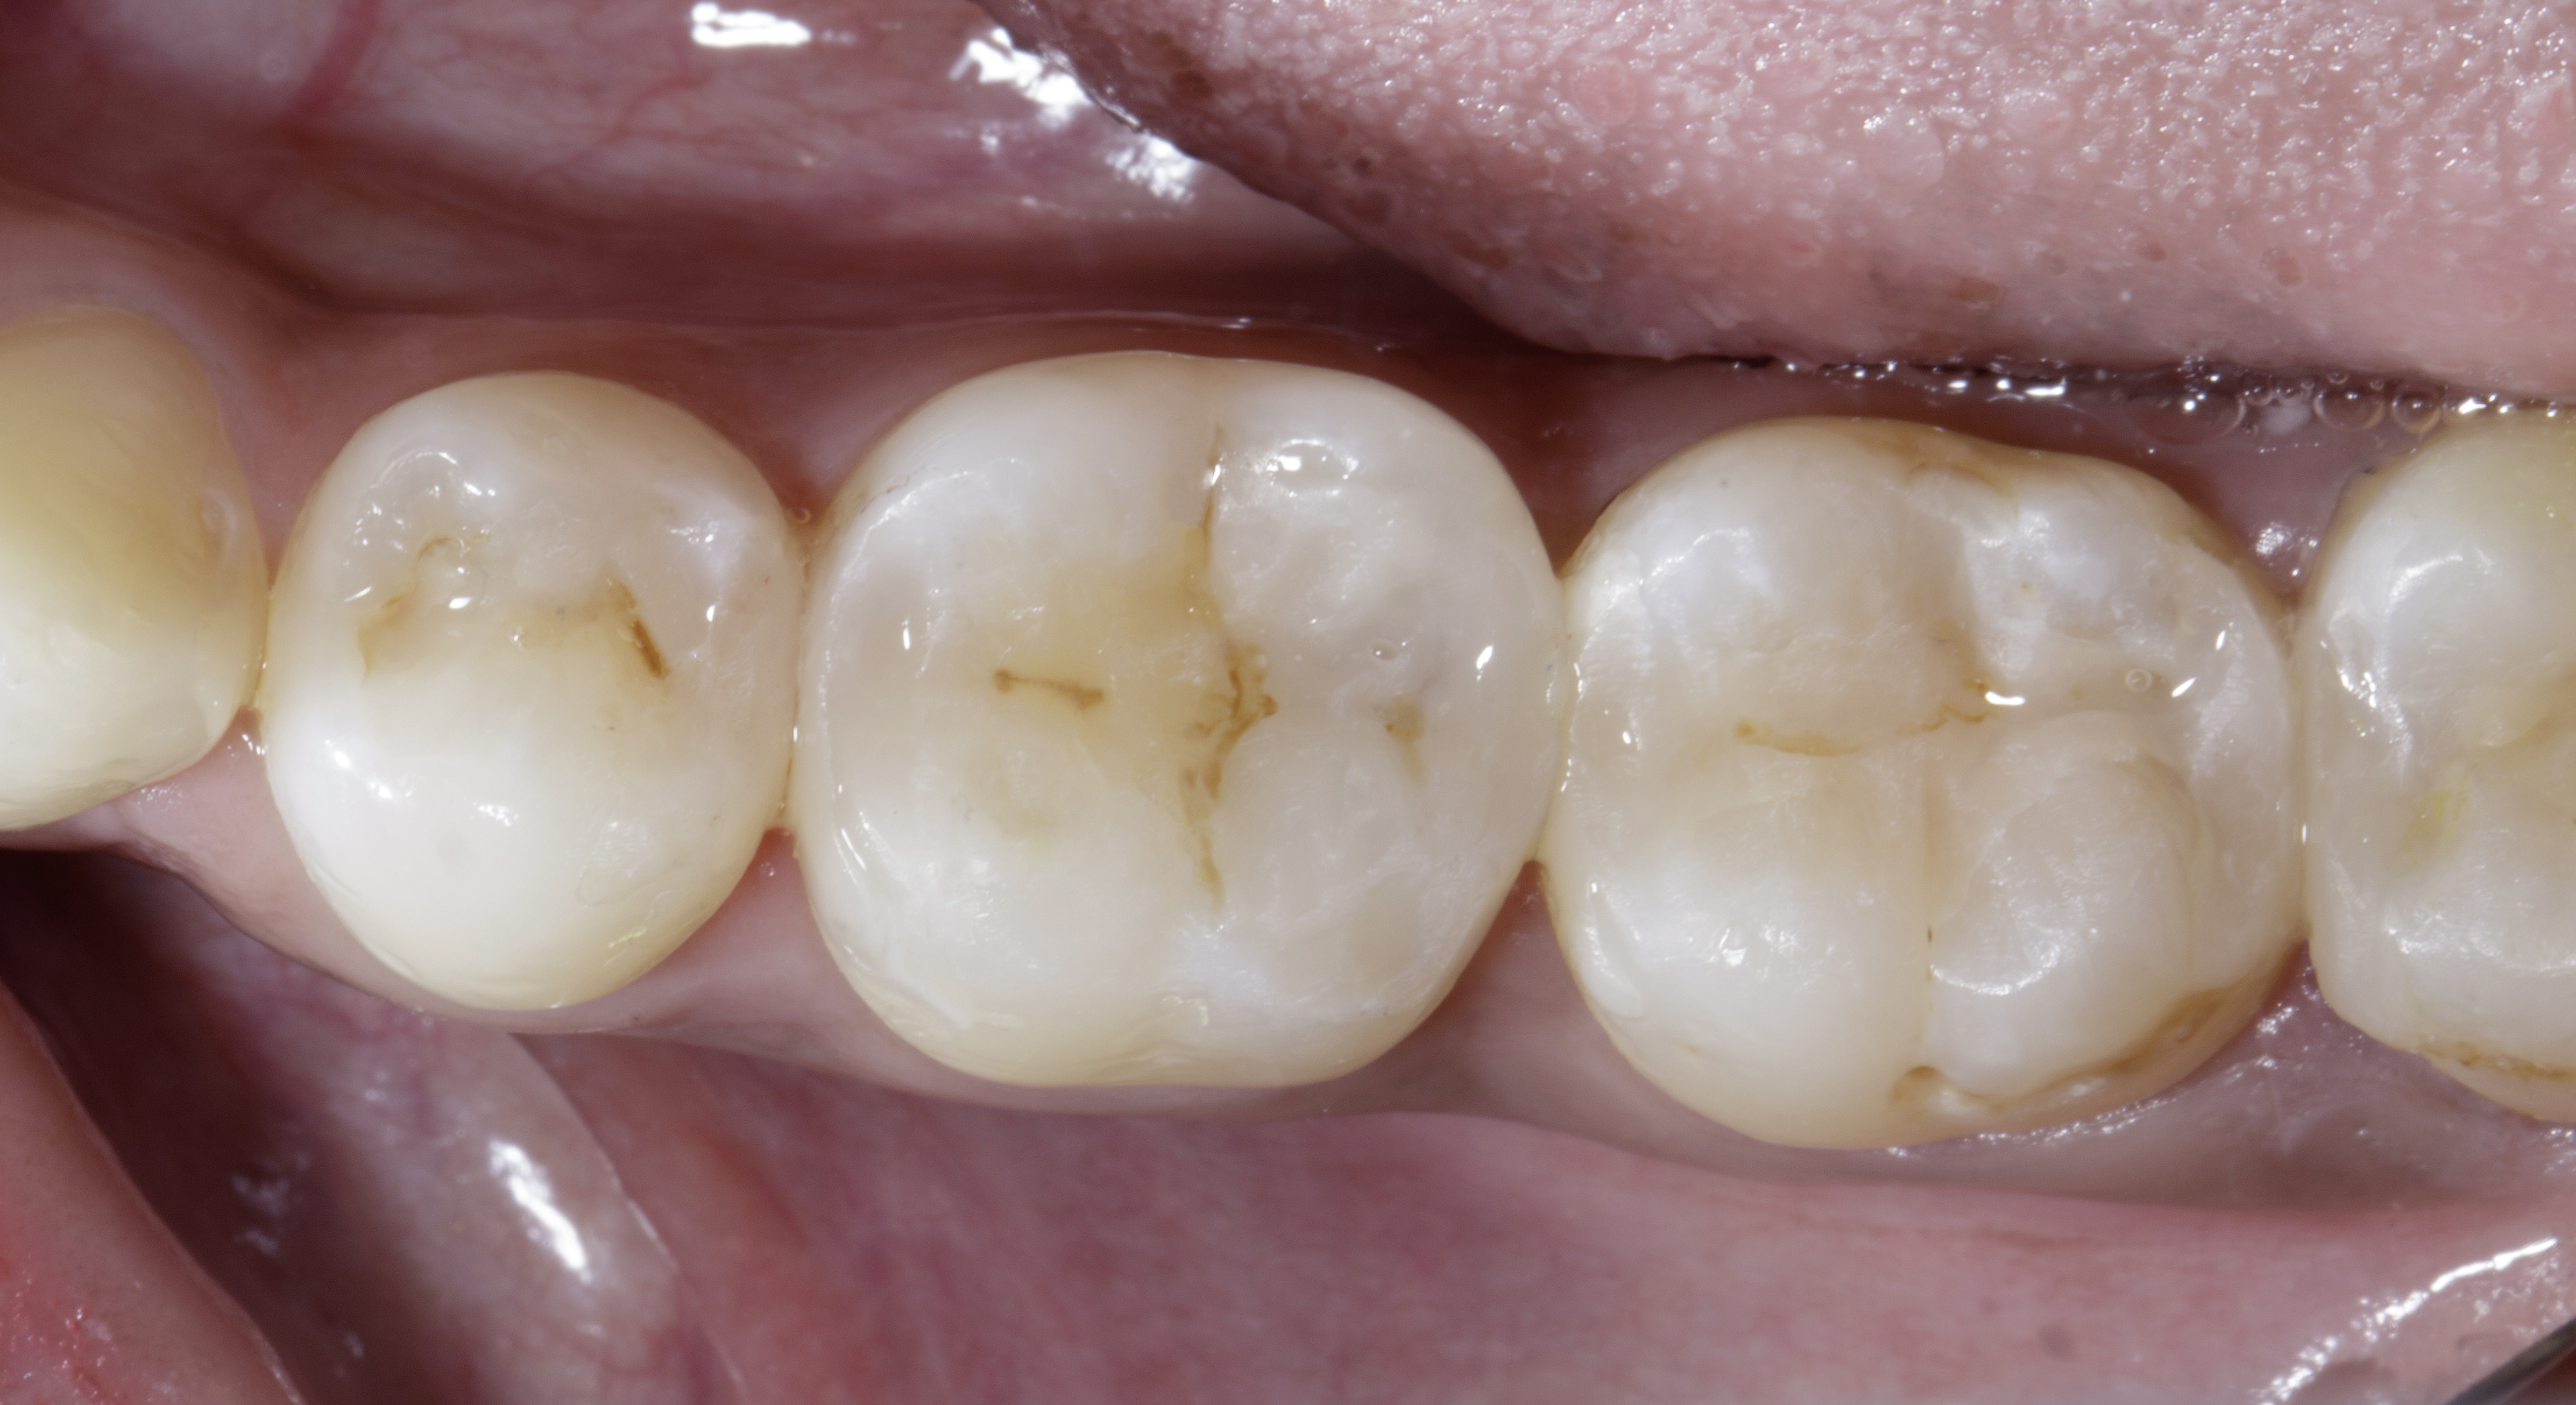

The rubber dam was removed, and high points were checked using 40-micron paper, followed by 8-micron foil in static occlusion. For dynamic occlusion, 200-micron paper was used, and adjustments were made to the cuspal slopes and non-functional cusps.

Figure 10. Before removal of rubber damFigure 11. IOPA to check no overhangs.

The quadrant restorative approach using the Garrison Quad Matrix System allowed precise reconstruction of proximal contacts, anatomical contour, and occlusal morphology in multiple adjacent Class II lesions. By first converting extensive MOD cavities into controlled Class I preparations through incremental wall build-up, polymerization shrinkage stress was minimized and tooth structure was preserved. The combination of Shofu Injectable XSL and Beautifil LS II packable composites, along with selective use of short-fibre composite, provided excellent marginal adaptation and structural reinforcement. This technique proved to be highly predictable, time-efficient, and minimally invasive, making it an ideal protocol for restoring multi-surface posterior defects while ensuring long-term functional stability and aesthetics.

Figure 12. Post op after 15 days.Figure 13. Buccal view, Post of after 15 days shows healthy gums with papilla filled with ideal contacts and contours.